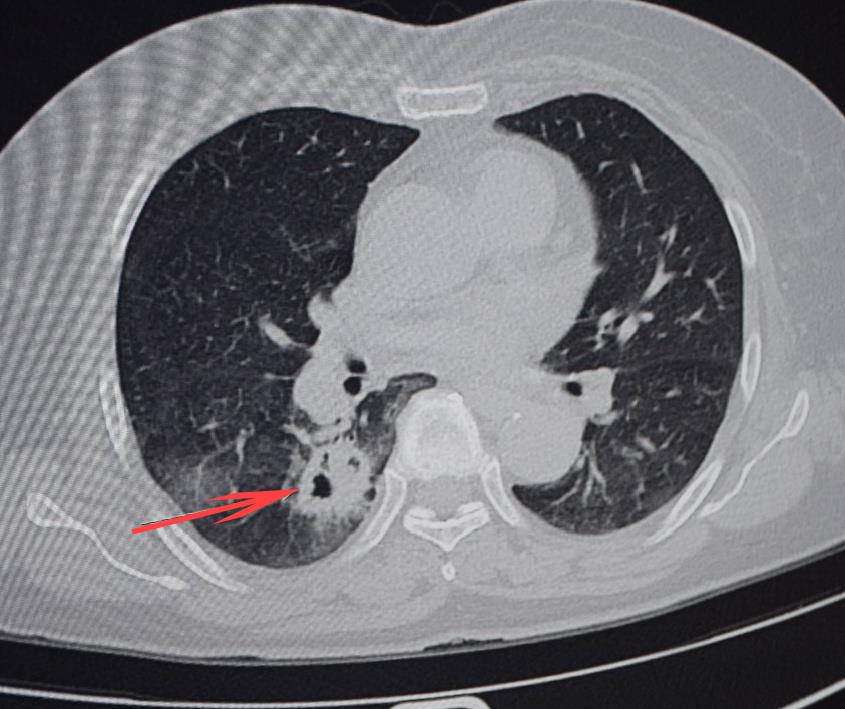

方女士十分不解,“骨头怎么化了,难不成身体里长了虫子,虫子把骨头吃掉了?”在随后的腰椎检查中,医生发现,不仅髋关节发生病理性溶骨,腰骶椎等区域也都有骨质破坏,结合肺部CT检查,经会诊,确诊老人是患上了肺癌,是癌细胞“吃”掉了骨头。

王军会介绍,肺癌初期症状不明显,往往到了出现咳嗽、骨头酸痛等症状时,已是晚期。骨转移在肺癌病人中较为常见,其好发部位依次为肋骨、胸椎、腰椎、骨盆。像方女士这样骨转移的情况比较常见,这也是导致病情被忽视延误的一个原因。